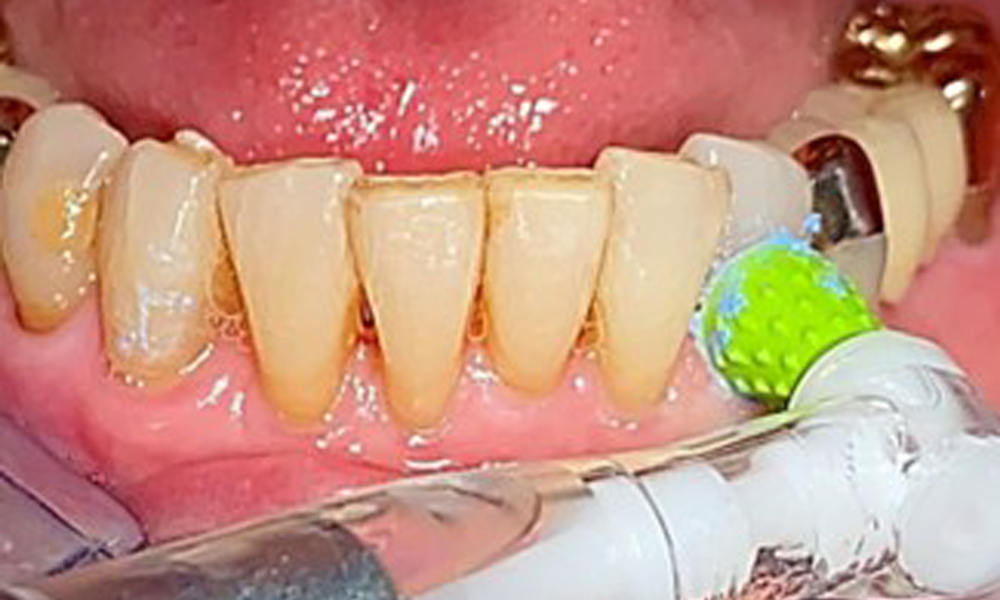

The patient was fitted with a combined removable maxillary telescopic prosthesis more than 25 years ago (Fig. 1, Fig. 2, Fig. 3) and is very happy with her dentures. The patient has an adequate fixed denture for the mandible (Fig. 4).

The dental findings are as follows: Combined removable implant and tooth-supported telescopic prostheses on implants 15, 13, 21, 23, 24, 25 and tooth 11 (Fig. 1, Fig. 2, Fig. 3). The patient was fitted with a fixed mandibular denture. Adequate bridges were present over 37 to 34 and 45 to 47 (Fig. 4), the crown margins were intact and there were no active caries. A composite filling with a marginal gap was present on tooth 43. There was mandibular gingival recession, exposing 1 to 3 mm of root surface. This also applies to 11.

A single-tufted brush is specifically recommended for the telescopic prostheses (Fig. 8) and the patient should be advised on the appropriate interdental brush size (Fig. 9). The patient has been implementing these recommendations for intraoral hygiene at home for many years and was encouraged to continue during the professional preventive dental appointment.

An air polishing system should be used with low-abrasive powder to remove biofilm from the restoration margins, interdental areas and implant surfaces (Fig. 12). Selective polishing (Fig. 13) should be used to smooth any less sensitive areas, as this decreases bacterial reattachment (9).